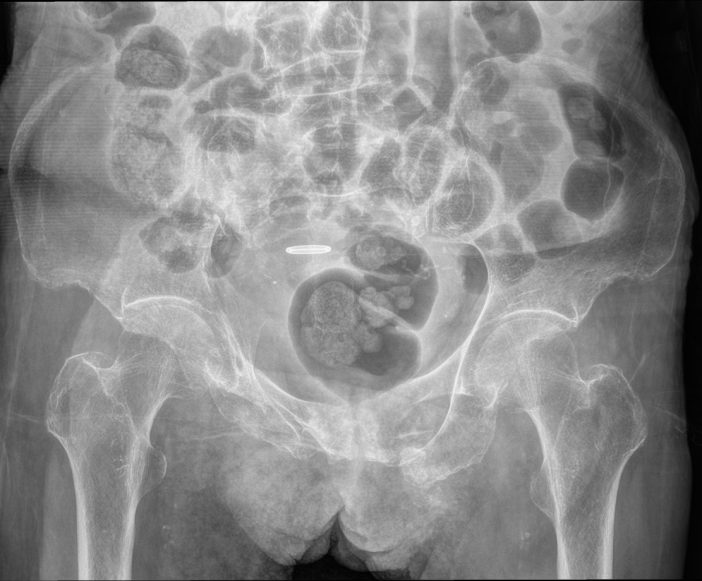

去年底,88岁的许奶奶时常感到全身疼痛,已持续两月余。到泰康同济完善相关检查后被诊断为左耻骨上下支病理性骨折。经多学科会诊排除了肿瘤转移的可能,考虑主要由骨质疏松引发。

因为担心许奶奶年龄较大,家属选择了保守治疗。但她出院后疼痛逐渐加重,并且日常活动严重受限,于2026年1月再次入院。复查骨盆CT显示,其不仅左侧骨折未愈,右侧髂骨也出现新骨折,吴大清查看患者情况后考虑骨盆环不稳定,卧床保守治疗效果不佳,建议手术治疗。